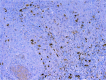

Materials and methods: Sixty primary skin SCC specimens were incubated with anti-CD8 (clone SP57) rabbit monoclonal antibody and anti-CD25 (clone 4C9) mouse monoclonal antibody.

Results: The ratio of the intratumoral∕peritumoral CD4+ CD25+ forkhead box protein p3 (Foxp3) lymphocytes was 0.46, emphasizing that at tumor margins, where tumor aggressiveness is higher, these lymphocytes subpopulations facilitate tumor progression. The comparative analysis of the tumor microenvironment profile revealed that in the case of intratumoral immune response, the number of Tc-type lymphocytes (CD8+) was 3.34 times higher compared to Treg lymphocytes (p<0001). In the peritumoral area, the number of Tc lymphocytes was 5.05 times higher compared to Treg lymphocytes (p<0001).